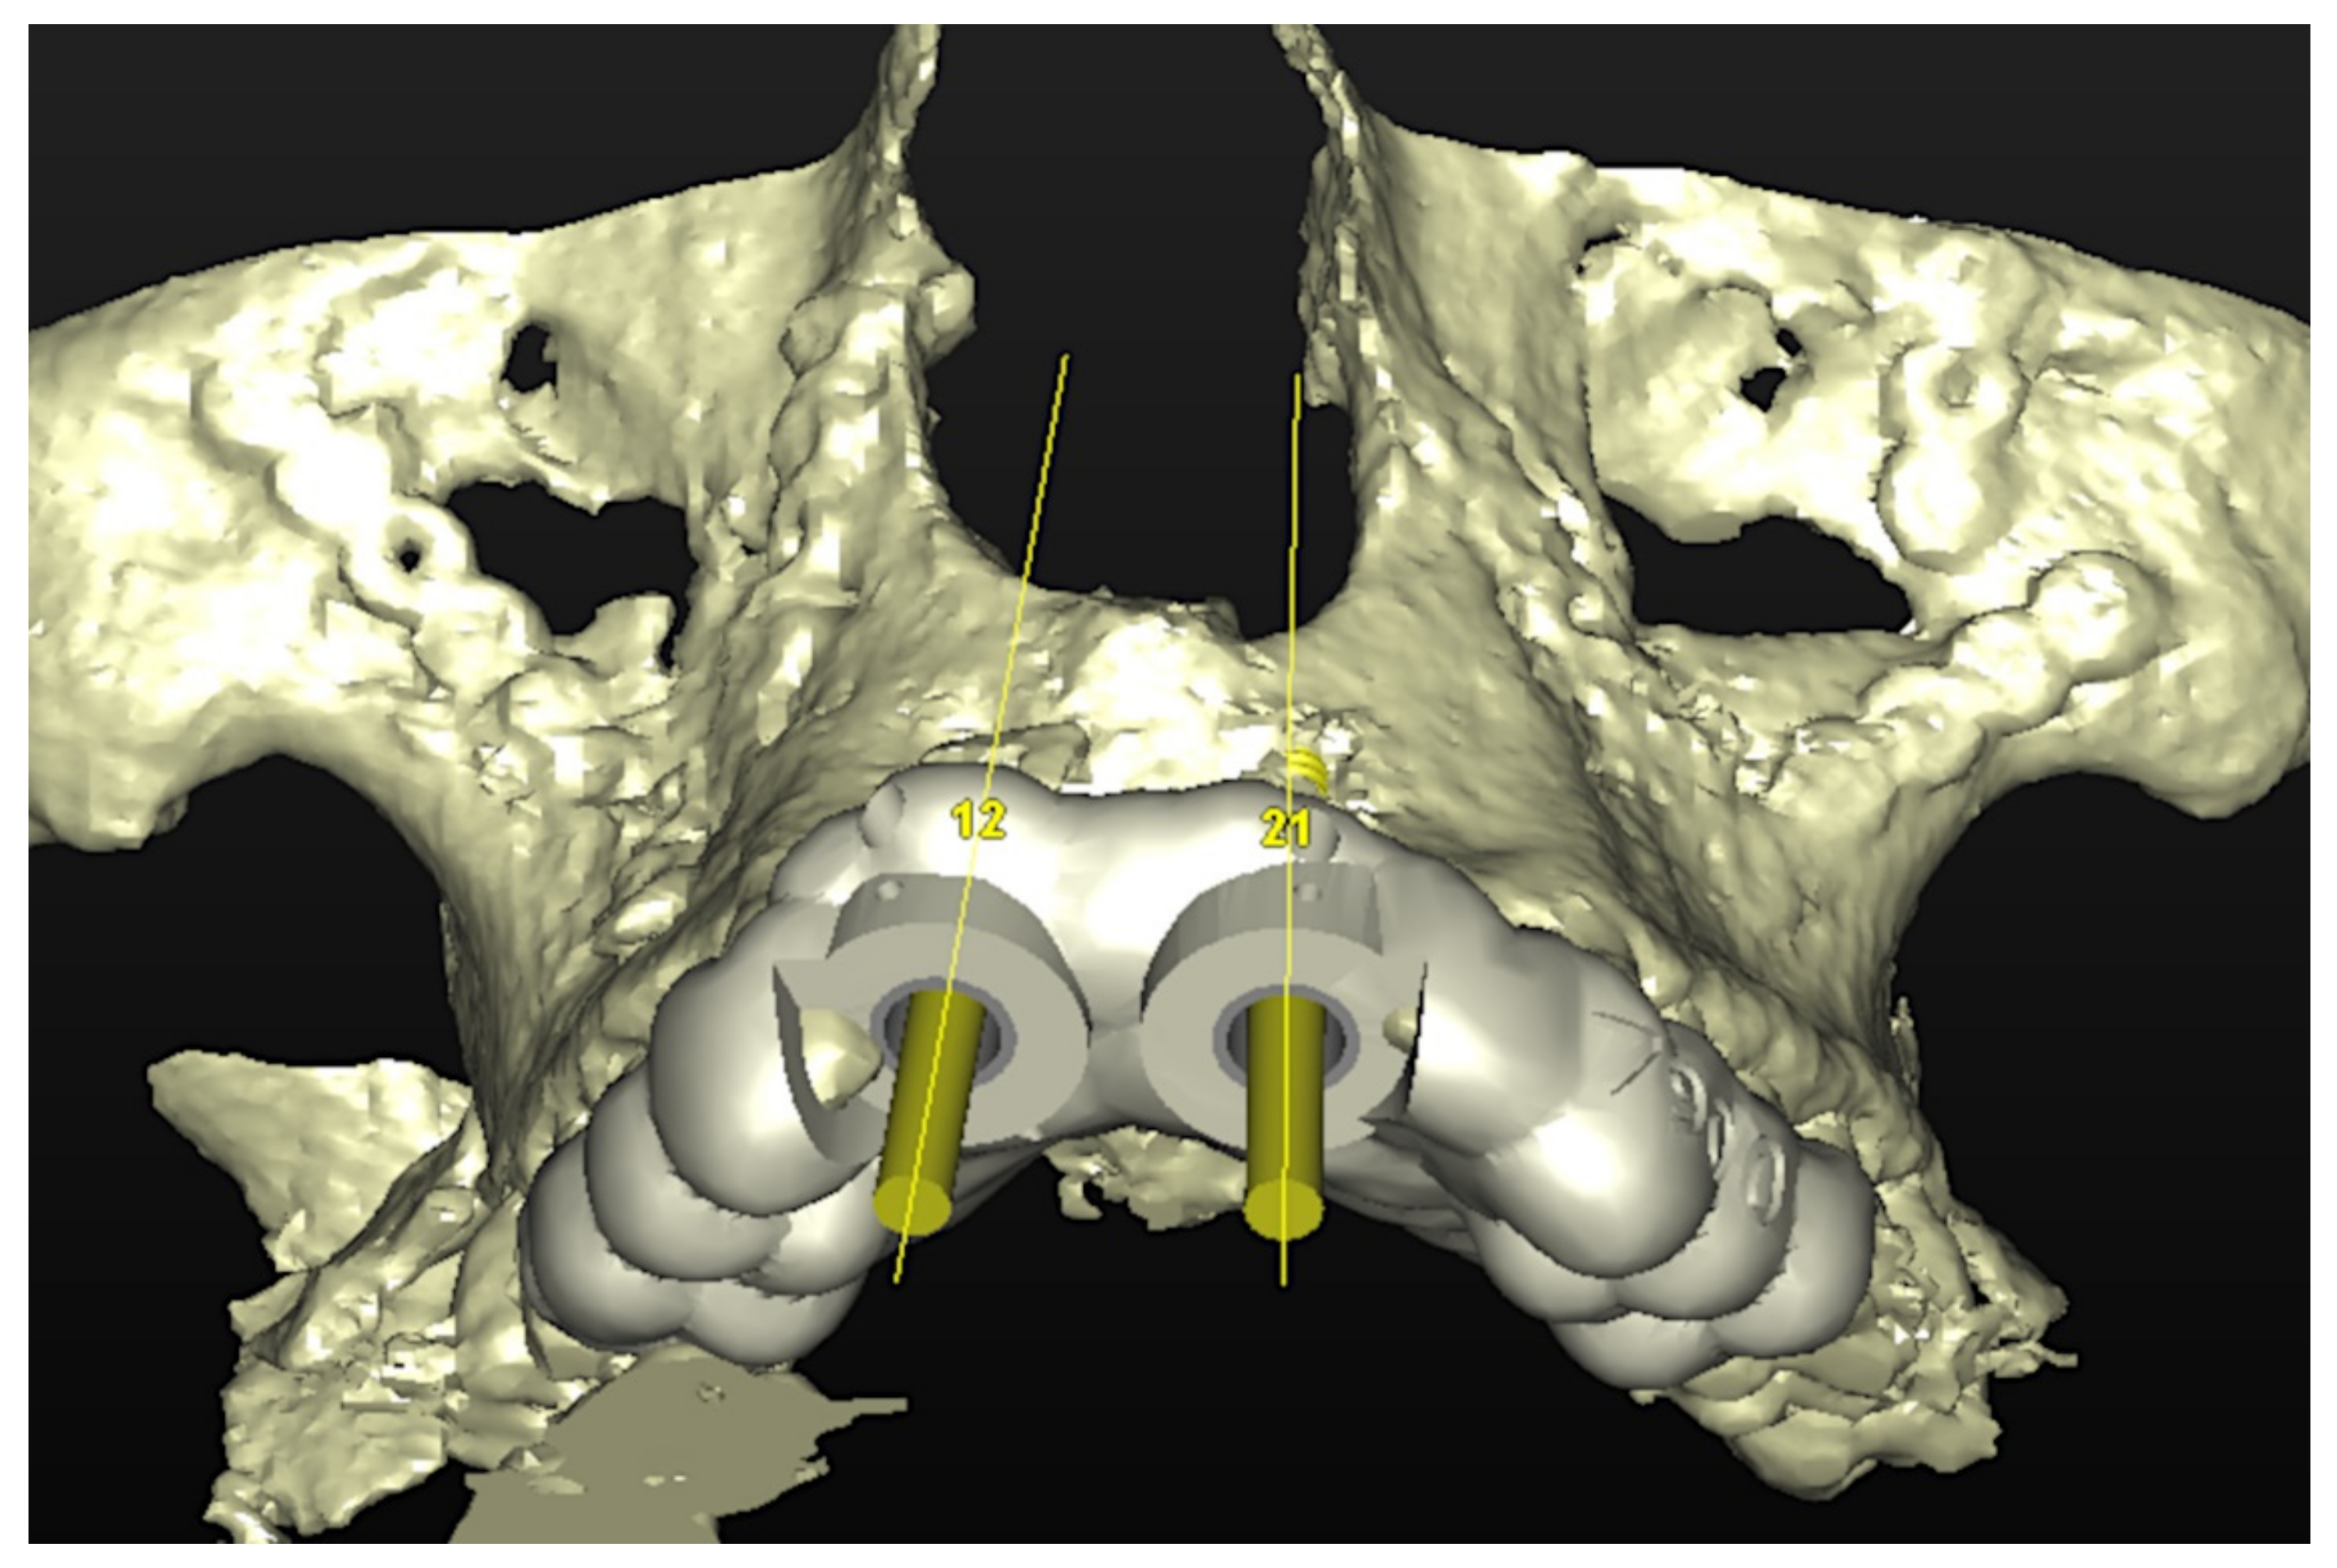

6.1.3. Image Segmentation and Virtual Planning:

6.1.4. Intra-Operative Documentation: